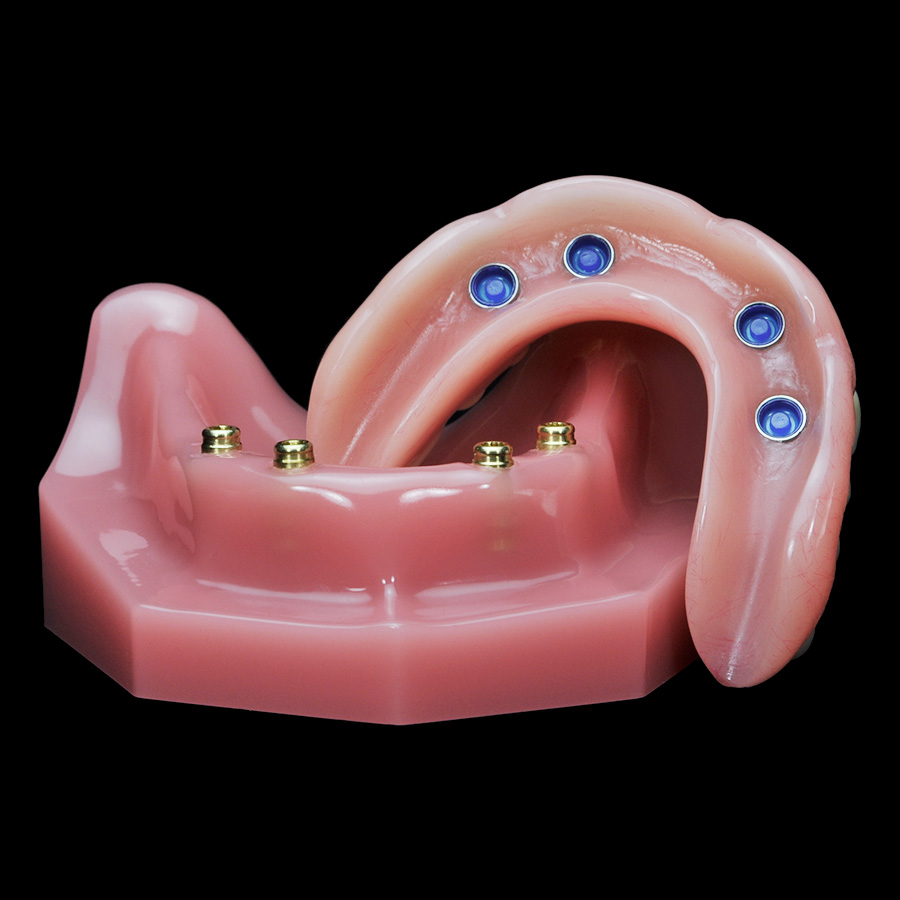

Современные съемные протезы на локаторах: Фото и примеры